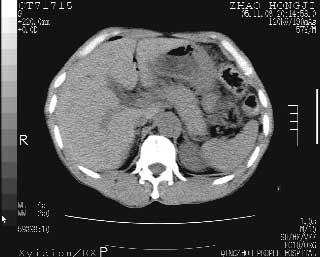

临床资料:男性,57岁,上腹部疼痛并5天,突然加重并延及全腹伴恶心5小时入院。胰淀粉酶化验在正常范围。检查:腹肌紧张,全腹压痛、反跳痛,尤以右上腹部为著。肠鸣音减低。血常规:wbc14.6x10/9, n:11.3x10/9 ,血压:135/90mmhg. 胸部透视:腹部肠腔轻度张气,未见其它异常改变。

胰腺形态规则,胰周脂肪间隙清晰,结合临床可排除急性胰腺炎

从图提示我同意空腔脏器穿孔的诊断,来源肠道{由于病程较短,故没能见到肠系膜聚局的征象}。

肝缘见少许气体,胰尾部见少许气体包饶(蓝色圈),12指肠上部或球部邻近胆囊周边也可见少许气体影(黄色圈),并忖托出胆囊壁,12指肠远段肠道内未见明显气体(白色箭)。

肝脏前缘见少量积气、胰尾部见少许气体包饶,肾前筋膜未见增厚,临床淀粉酶不高,意见:上消化道穿孔。

消化道穿孔。12指肠球部周和胰周积气考虑12指肠穿孔可能性大。

入院3小时后行剖腹探查术,见腹腔内大量脓性混浊液约1000ml,十二指肠球部溃疡穿孔,溃疡面约2.5x2cm,穿孔直径约0.6cm。胃内容物外益,周围组织炎性水肿明显。行十二指肠穿孔修补术。术后诊断:

1、十二指肠溃疡穿孔

2、弥漫性腹膜炎

对于少量的腹腔游离气体,ct检查较普通透视有绝对的优势,它不仅可以看到肝脏前上缘的气体,而且还能够看到小网膜区的游离气体。从而可以肯定诊断。各位分析战友的很好,感谢大家的参入!